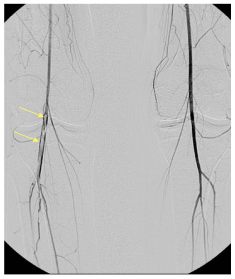

Fig. 38.5 Artériographie des membres inférieurs dans un contexte d’ischémie aiguë de la jambe droite.

On met en évidence une image lacunaire rubanée, à sommet arrondi, en rapport avec un caillot (embolie) étendu de l’artère poplitée au trépied jambier.

Source : CERF, CNEBMN, 2022.